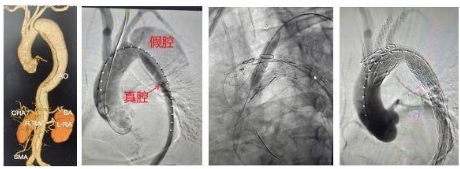

患者為一名40歲男性,高血壓急癥伴胸部不適入院,血壓高達(dá)220/110mmHg,胸部CTA提示主動(dòng)脈夾層,該患者主動(dòng)脈弓角度比較大,破口緊鄰左鎖骨下動(dòng)脈,支架錨定區(qū)不足,直接覆膜支架覆蓋很可能出現(xiàn)側(cè)漏不能完全隔絕破口,導(dǎo)致手術(shù)失敗。需要支架向左鎖骨下和左頸總動(dòng)脈近心端拓展,而這樣就會(huì)導(dǎo)致覆蓋堵塞左鎖骨下和左頸總動(dòng)脈必然帶來(lái)災(zāi)難性后果。

因此,瑞康醫(yī)院心內(nèi)科團(tuán)隊(duì)決定通過(guò)主動(dòng)脈支架體外開(kāi)窗方法保住左鎖骨下和左頸總動(dòng)脈,根據(jù)術(shù)中測(cè)量結(jié)果和3D打印模型,選擇主動(dòng)脈覆膜支架體外開(kāi)窗,取左頸總動(dòng)脈及左鎖骨下動(dòng)脈開(kāi)窗并縫內(nèi)分支支架一枚,同時(shí)行支架束徑。其間,自右股動(dòng)脈入路送入主動(dòng)脈支架至弓部預(yù)定位置半釋放,分別經(jīng)左頸總動(dòng)脈及左肱動(dòng)脈入路,導(dǎo)絲配合導(dǎo)管超選開(kāi)窗洞口至主動(dòng)脈支架內(nèi),沿導(dǎo)絲送入兩枚分支支架,分別釋放主動(dòng)脈及分支支架。術(shù)后,造影顯示各分支動(dòng)脈暢通,夾層完全消失無(wú)內(nèi)漏。手術(shù)完美結(jié)束。

主動(dòng)脈夾層是一種極其危險(xiǎn)的心血管急癥,主要表現(xiàn)為突發(fā)性劇烈胸背痛。這種疾病就像輪胎內(nèi)胎破了個(gè)口子,血液從血管最內(nèi)層(內(nèi)膜)的破口沖進(jìn)血管壁中間層,像吹氣球一樣把血管壁撐開(kāi)形成血腫,隨著血液不斷沖擊,血管壁的內(nèi)層和中層被撕裂分離。此時(shí),血管被撕開(kāi)形成真假兩個(gè)通道,即真腔和假腔,兩者之間被撕裂的血管壁(內(nèi)膜片)隔開(kāi)。